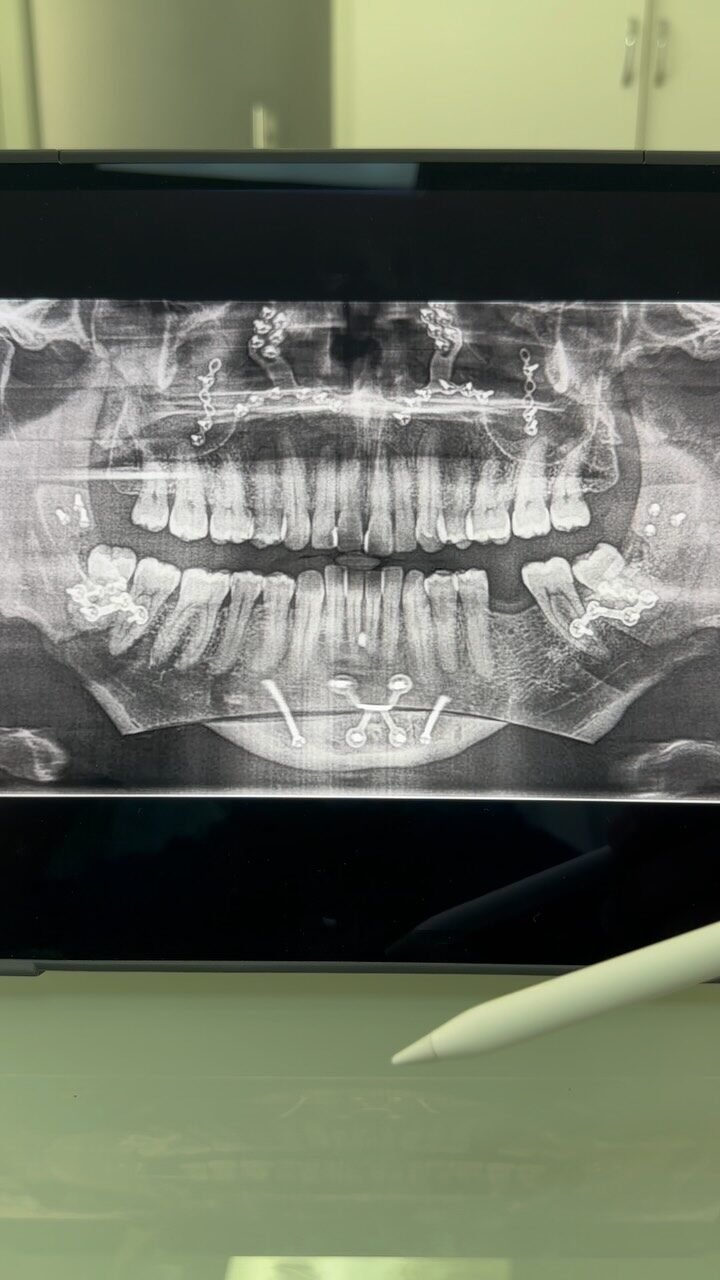

Você sente dificuldade para morder, falar ou até mesmo respirar corretamente? A Cirurgia Ortognática pode ser a solução! Esse procedimento corrige alterações ósseas no maxilar e mandíbula, melhorando a função mastigatória, a harmonia facial e a qualidade de vida.

Mandíbula muito projetada, retraída ou mordida cruzada podem afetar a harmonia facial e prejudicar a mastigação.

Sim. Eles são usados antes da cirurgia para garantir o melhor encaixe durante a cirurgia e durante algum tempo pós cirurgia para otimizar o ajuste final da dentição.